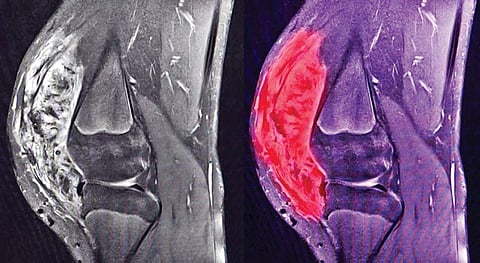

Often, various other tests such as Immunohistochemistry and Molecular profilling are required to obtain the correct diagnosis. A CT Scan, MRI scan or PET CT scan may also be required to ascertain the characteristics of the tumour and the extent of spread. The main treatment modalities are surgery, radiotherapy, chemotherapy and targeted therapy. Sometimes a combination of these treatment are required depending upon the nature and stage of sarcoma. Sarcoma diagnosed in early stages are generally curable, but not so in advanced stages. Limb preservation surgeries are generally attempted and have become standard practise wherever possible. In advanced stages chemotherapy and targeted therapies are the mainstay on treatment.